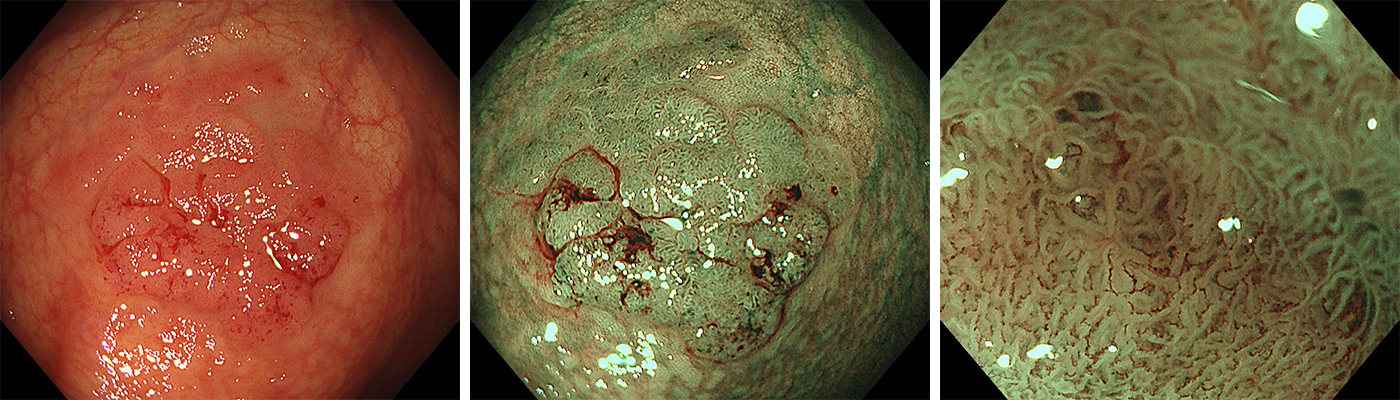

一般的には大腸カメラ検査と呼ばれている大腸内視鏡検査は、肛門から細長いスコープを入れて直腸から結腸、盲腸のほか、小腸の回腸末端までを直接観察できます。そのため微小な病変も見つけやすく、高精度な検査です。